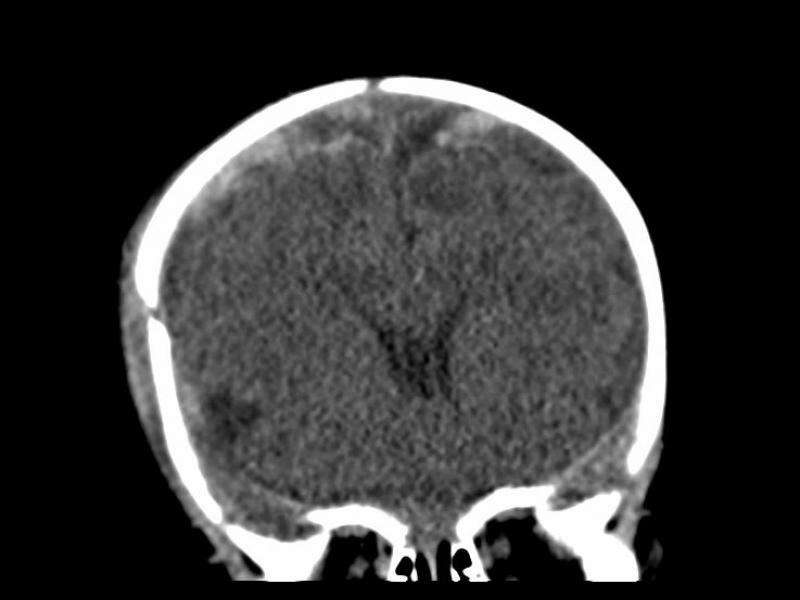

What's the diagnosis? By Dr. Angela Ugorets

September 25 2019

A 2 month old reportedly rolled off the bed and EMS was